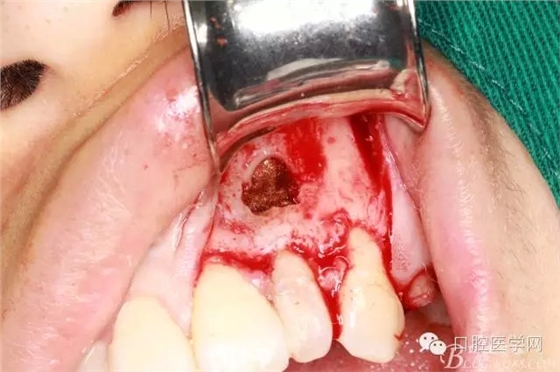

刮凈囊腫

繼續(xù)去骨暴露牙根

牙根露出3mm左右因?yàn)楦虚L度

沖洗干凈開窗處

根切后可見開窗處清理干凈

刮出囊腫及牙根2.5MM